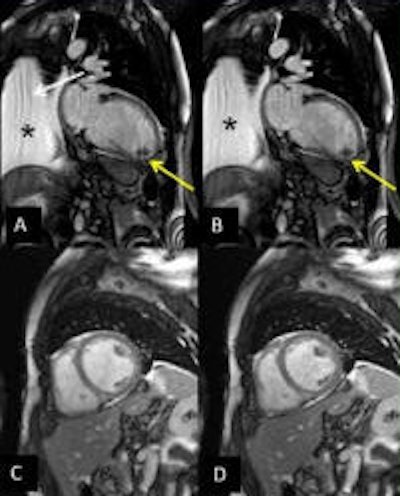

The study team implemented its single breath-hold multislice CS cine sequence on a 1.5-tesla MR system (Magnetom Aera, Siemens Healthcare), acquiring three long-axis and four short-axis slices over 14 heartbeats in a single breath-hold. Temporal and spatial resolution was 30 msec and 1.5 x 1.5 mm2, respectively. Data were analyzed using Argus 4DVF software (Siemens Healthcare).

The CS acquisitions maintained high image quality in 94% of subjects, maintaining qualitative accuracy in LV systolic function (above) and with excellent correlation (r = 0.96, slope = 0.97, p < 0.00001). Finally, intra-/interobserver agreement for all CS parameters was good (slopes: 0.93-1.06, r: 0.90-0.99), the group reported.